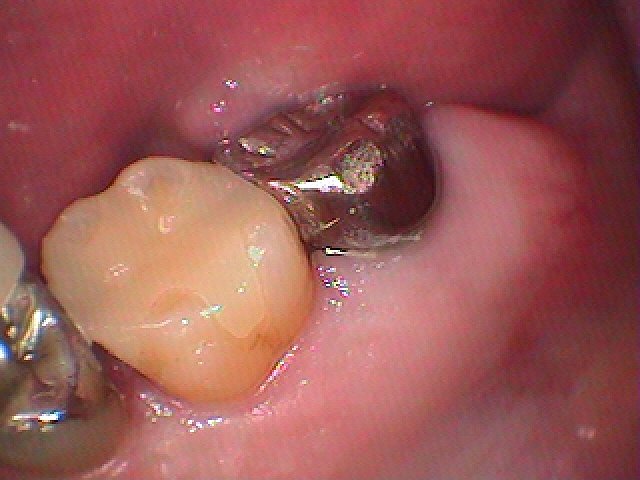

左上6番隣接部に虫歯 銀歯をはずして虫歯治療 |お知らせ |広島市安佐南区の歯科医院 左上6番隣接部に虫歯 銀歯をはずして虫歯治療 トップ お知らせ・ブログ お知らせ 左上6番隣接部に虫歯 銀歯をはずして虫歯治療 左上6番隣接部に虫歯 銀歯をはずして虫歯治療 左上6番の遠心部が虫歯になっています この銀歯をはずしていきます 少し黒く虫歯になっています 遠心部に虫歯が存在しています 遠心部の虫歯になります 虫歯を除去していきました セレックセラミックにてきれいに修復しています このようにきれいに白いセラミックにて修復できました 喜んでいただきました Web診療予約 初めての方へ 選ばれ続ける理由 院内設備について 歯が痛いしみる一般歯科 歯がぐらぐらする歯周病 健康な歯を保ちたい予防歯科 子供の虫歯予防をしたい小児歯科 銀歯をセラミックに審美歯科 白い歯を目指しませんか?ホワイトニング 矯正専門医がいるので安心矯正歯科 抜けた歯を補いたいインプラント・入れ歯 医院案内 スタッフ紹介 メリィハウス歯科クリニックオフィシャルホームページ ラベンダー歯科クリニックオフィシャルホームページ お知らせ・ブログ ホーム 診療科目 一般歯科 歯周病治療 予防治療 小児歯科 審美治療 ホワイトニング 矯正歯科 入れ歯・インプラント マウスピース矯正 初めての方へ 院長・スタッフ 設備紹介 医院案内・アクセス メニューを閉じる